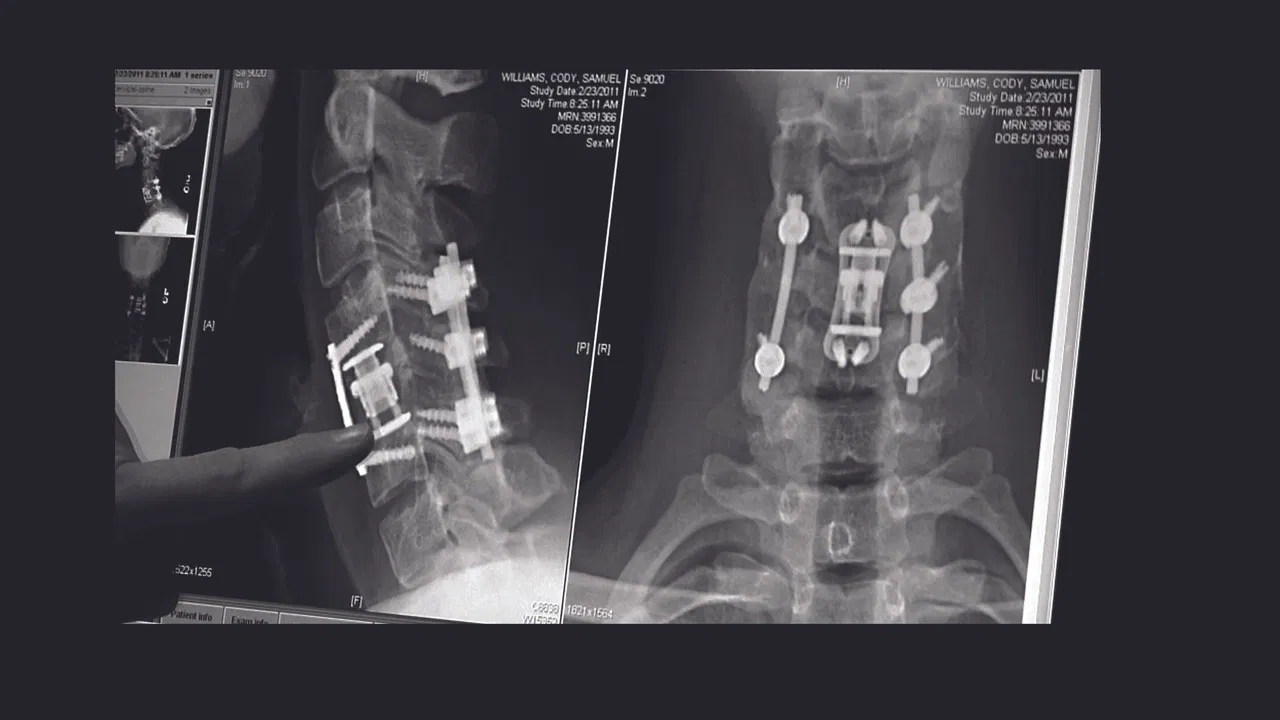

The compelling, heart-wrenching story of high school football star Chris Carnales, whose life changed when he became paralyzed after breaking his neck in a football game. Chris soon learned of others who suffered similar injuries and, with the help of his father, overcame tremendous pain to start an organization with one goal in mind: get immediate help to other victims and their families. He called it Gridiron Heroes.

2011 / 1 hr 30 minThe compelling, heart-wrenching story of high school football star Chris Carnales, whose life changed when he became paralyzed after breaking his neck in a football game. Chris soon learned of others who suffered similar injuries and, with the help of his father, overcame tremendous pain to start an organization with one goal in mind: get immediate help to other victims and their families. He called it Gridiron Heroes.